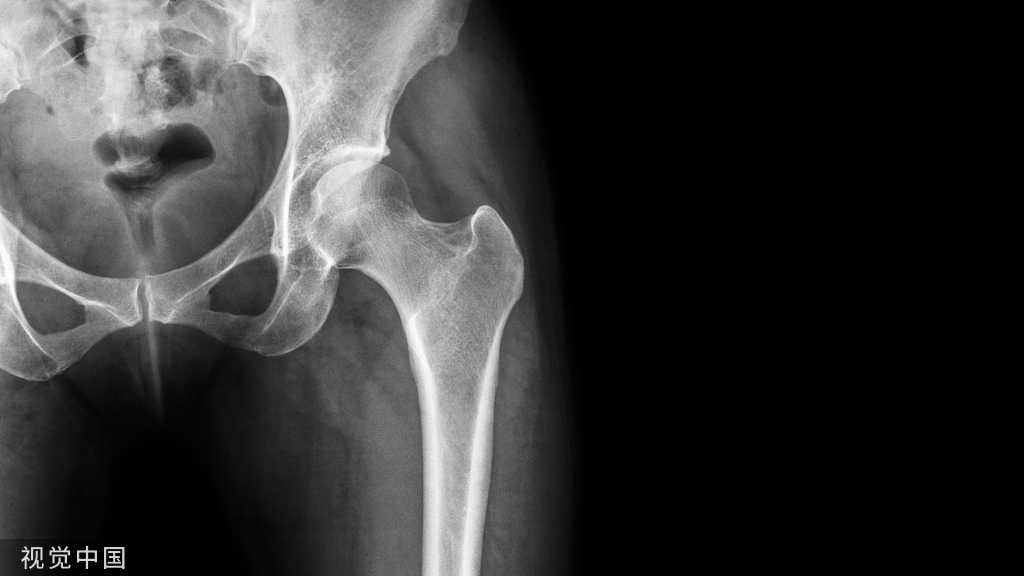

66岁女患者,因为膝关节疼痛到影像科检查,却偶然发现右侧股骨下端有类似“爆米花”样的异常信号。

影像表现:平片、CT所见股骨下段髓腔内可见爆米花样高密度灶,边缘清楚。MRI示病灶T1呈低信号,T2呈不均匀高信号,符合软骨小叶信号。

诊断意见:考虑右股骨内生软骨瘤。

X线表现:一般呈中心性生长。可见边缘清晰的类圆形骨质破坏区,多有硬化缘与正常骨质相隔,邻近骨皮质变薄膨出,破坏区可见散在的砂粒样钙化,这是软骨瘤主要的X线表现。